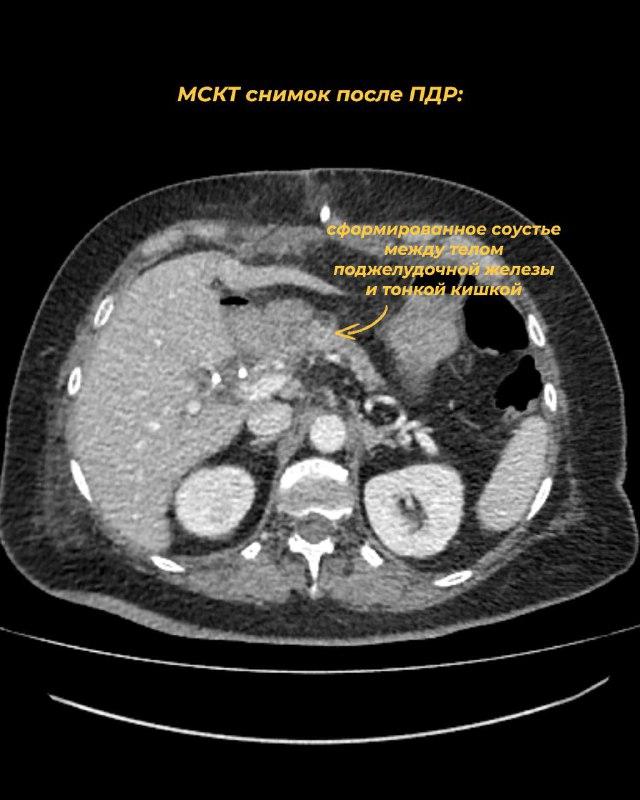

Панкреатодуоденальная резекция длилась около 7 часов, выполнена в полном объеме, радикально. Это была 15-я совместная ПДР отдела после его формирования в Иваново. Интраоперационных и послеоперационных осложнений нет. Пациентка выписана к своим близким.

Данный случай демонстрирует важность мультидисциплинарного подхода и командной работы в рамках специализированного онкологического учреждения. Компетенции отдела торакоабдоминальной онкохирургии ИвООД позволяют выполнять вмешательства высшей категории сложности пациентам Ивановской области.